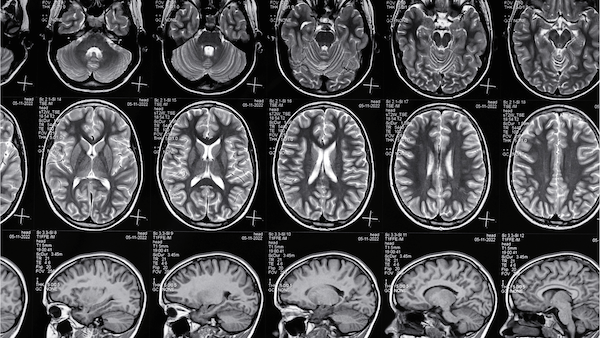

White Matter Injury (WMI)

is the most common brain injury in preterm infants. It is caused by inflammation and hypoxia, and leads to the loss of Oligodendrocyte Progenitor Cells (OPCs). This, in turn, disrupts myelination in the developing infant brain, and causes permanent motor and cognitive deficits - exemplified in severe cases by cerebral palsy.